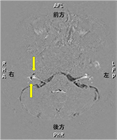

1. 著者らは2024年にGa(ガドリニウム)造影剤を用いずに内リンパ水腫をMRIで可視化することを世界で最初に報告した[2]